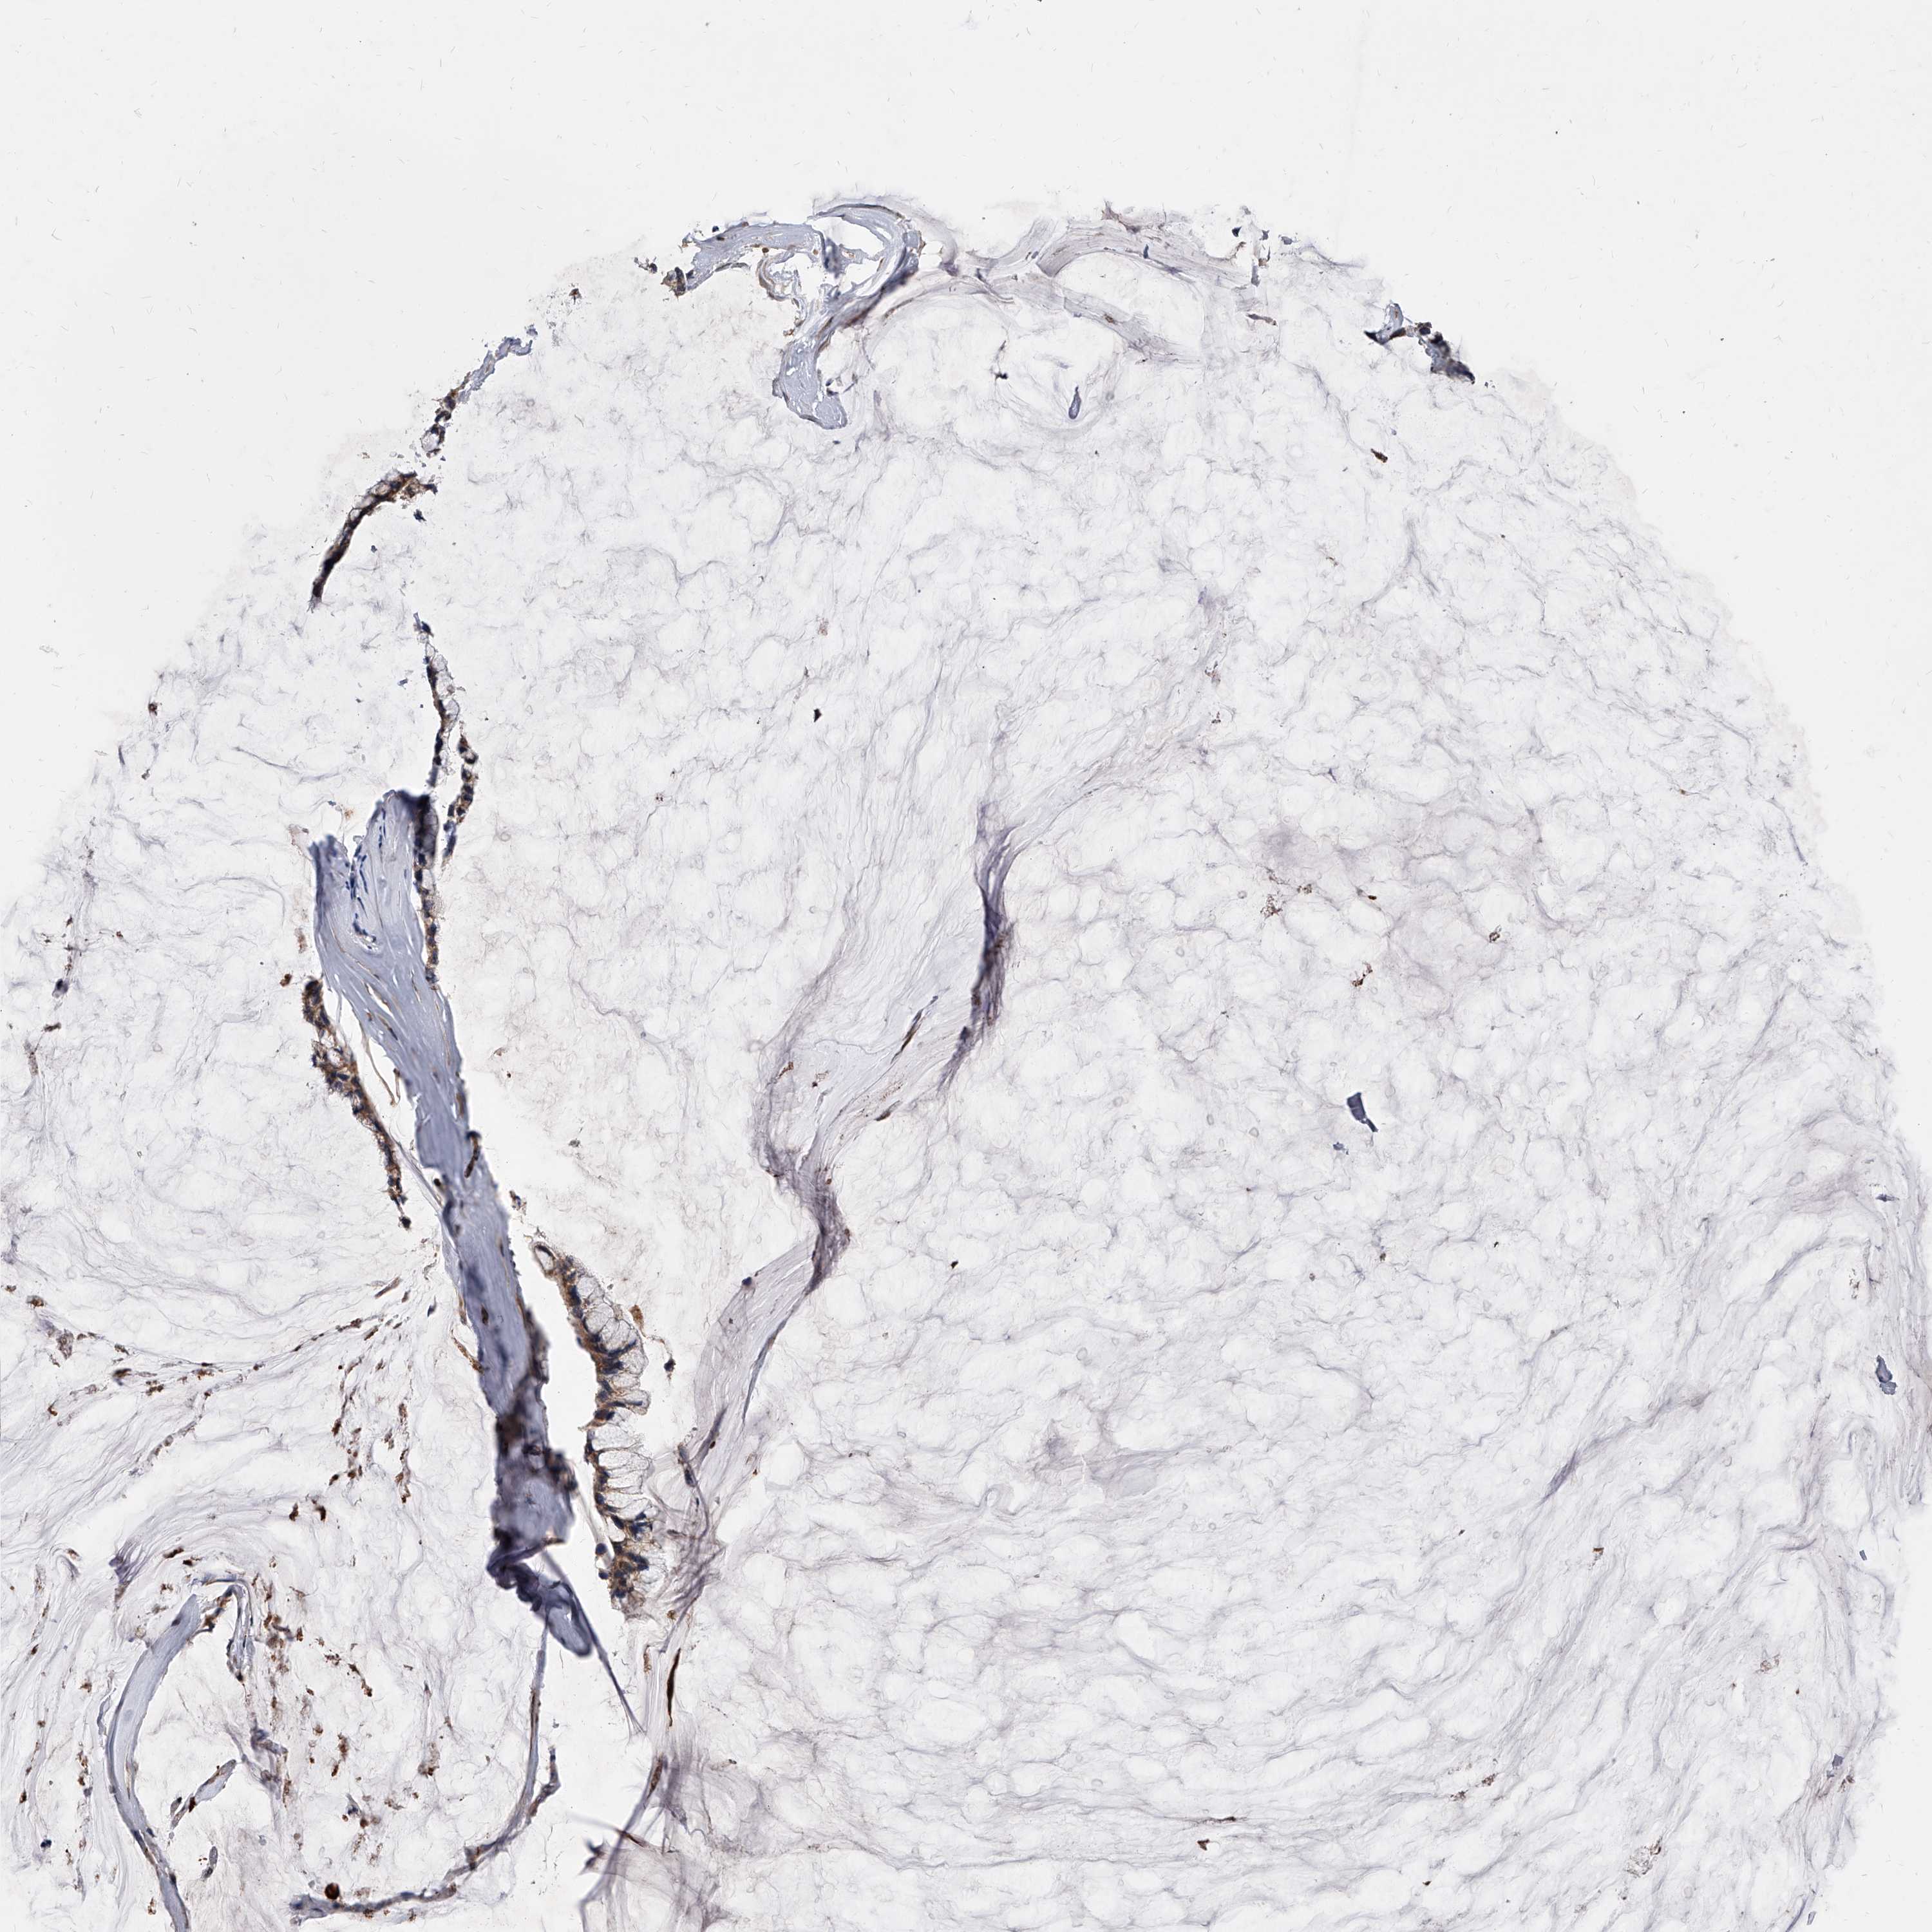

OVARIAN CANCER - Protein expressioni

A mouse-over function shows sample information and annotation data. Click on an image to view it in a full screen mode. Samples can be filtered based on level of antibody staining by selecting one or several of the following categories: high, medium, low and not detected. The assay and annotation is described here.

Note that samples used for immunohistochemistry by the Human Protein Atlas do not correspond to samples in the TCGA dataset.

Antibody stainingi

Antibody staining in the annotated cell types in the current human tissue is reported as not detected, low, medium, or high, based on conventional immunohistochemistry profiling in selected tissues. This score is based on the combination of the staining intensity and fraction of stained cells.

Each image is clickable and will lead to virtual microscopy that enables deeper exploration of all samples and also displays staining intensity scores, fraction scores and subcellular localization as well as patient and tissue information for each sample.

Antibody HPA029242

Cystadenocarcinoma, serous, NOS

Carcinoma, endometroid

Cystadenocarcinoma, mucinous, NOS

Carcinoma, NOS